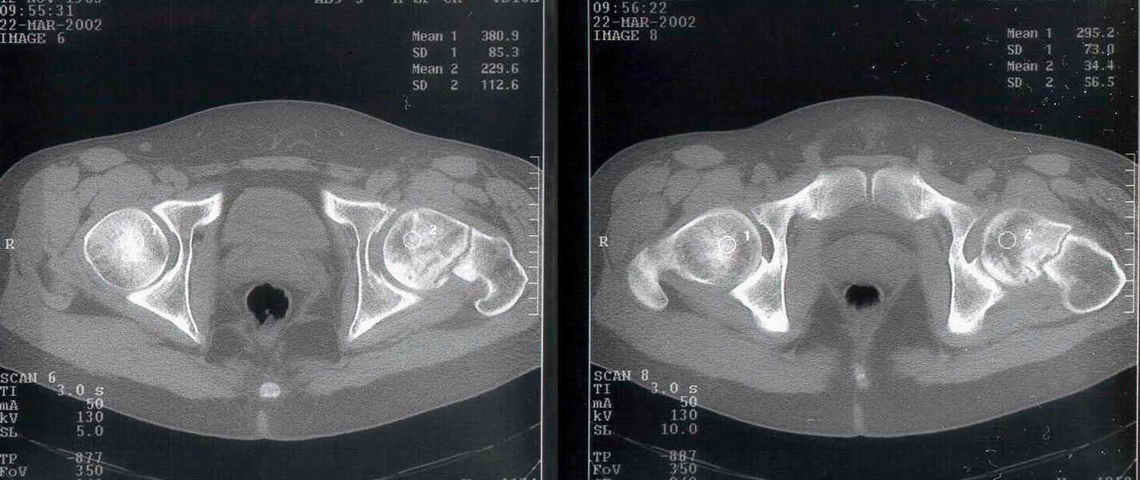

Уважаемый Александр! По 38-летнему пациенту. На томограмме имеются явные признаки асептического некроза. Этот процесс будет развиваться стремительно.

1-2 года и Вы вынуждены будете эндопротезировать пациента. Есть ли необходимость в дополнительной операции (остеотомии)? У 35-летнего пациента

Рентгенологические признаки пост травматического аваскулярного некроза по классификации Ficat / Arlet Stage 1. на мой взгляд DHS - без какой -либо остеотомии стабилизировало зону перелома, а сам процесс рассверливания шейки бедра съимитировал бы так называемую core decompression procedure, которая показана при 1-3 стадиях AVN.

At first is necesary take a Magnetic Resonance for the diagnosis de avascular necrosis.

I see zones of osteoporosis in the head and for this is necesary a vascular existence, then for me was necesary the MR.

You have a non union neck, avascualr necrosis and varus deformity.

Вчера сделали остеотомию, делали близко к тому, как на той картинке.

Картинка тут.

То, что получилось, в приложении (без такой красивой анимации, к сожалению